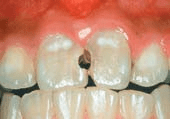

Figures 1 and 2 show cases of mild dental fluorosis (pictures provided by Dr Wendell Evans and Dr Ikreet Bal, the University of Sydney).

Figure 2: Mild dental fluorosis predominantly on the upper and outer thirds of the upper front teeth